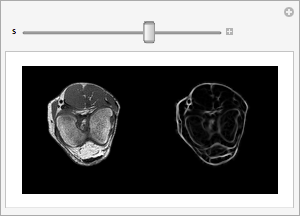

Renderização lado-a-lado de cada fatia do volume do joelho original e filtrado.